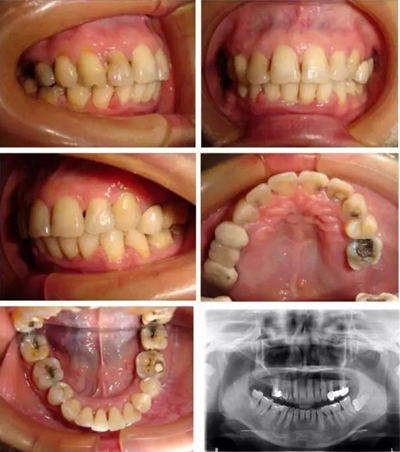

▲ 圖4 矯治26個月后,患者牙(牙合)像、曲面斷層、頭顱側(cè)位片及側(cè)面像

微種植體支抗均保持穩(wěn)定,前牙內(nèi)收明顯,面型得到改善,患者對矯治效果基本滿意。頭影測量分析顯示:U1-NA角、U1-NA距、L1-NB角、L1-NB距、上唇突度、下唇突度及面型角明顯減小,治療前后差異均具有統(tǒng)計學(xué)意義(P <0.05),而SNA、SNB、ANB、U6-PP、MP/FH治療前后差異無統(tǒng)計學(xué)意義(P >0.05)。